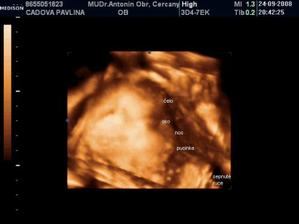

• 24.9.2008 – 4D ultrazvuk, potvrzena holčička